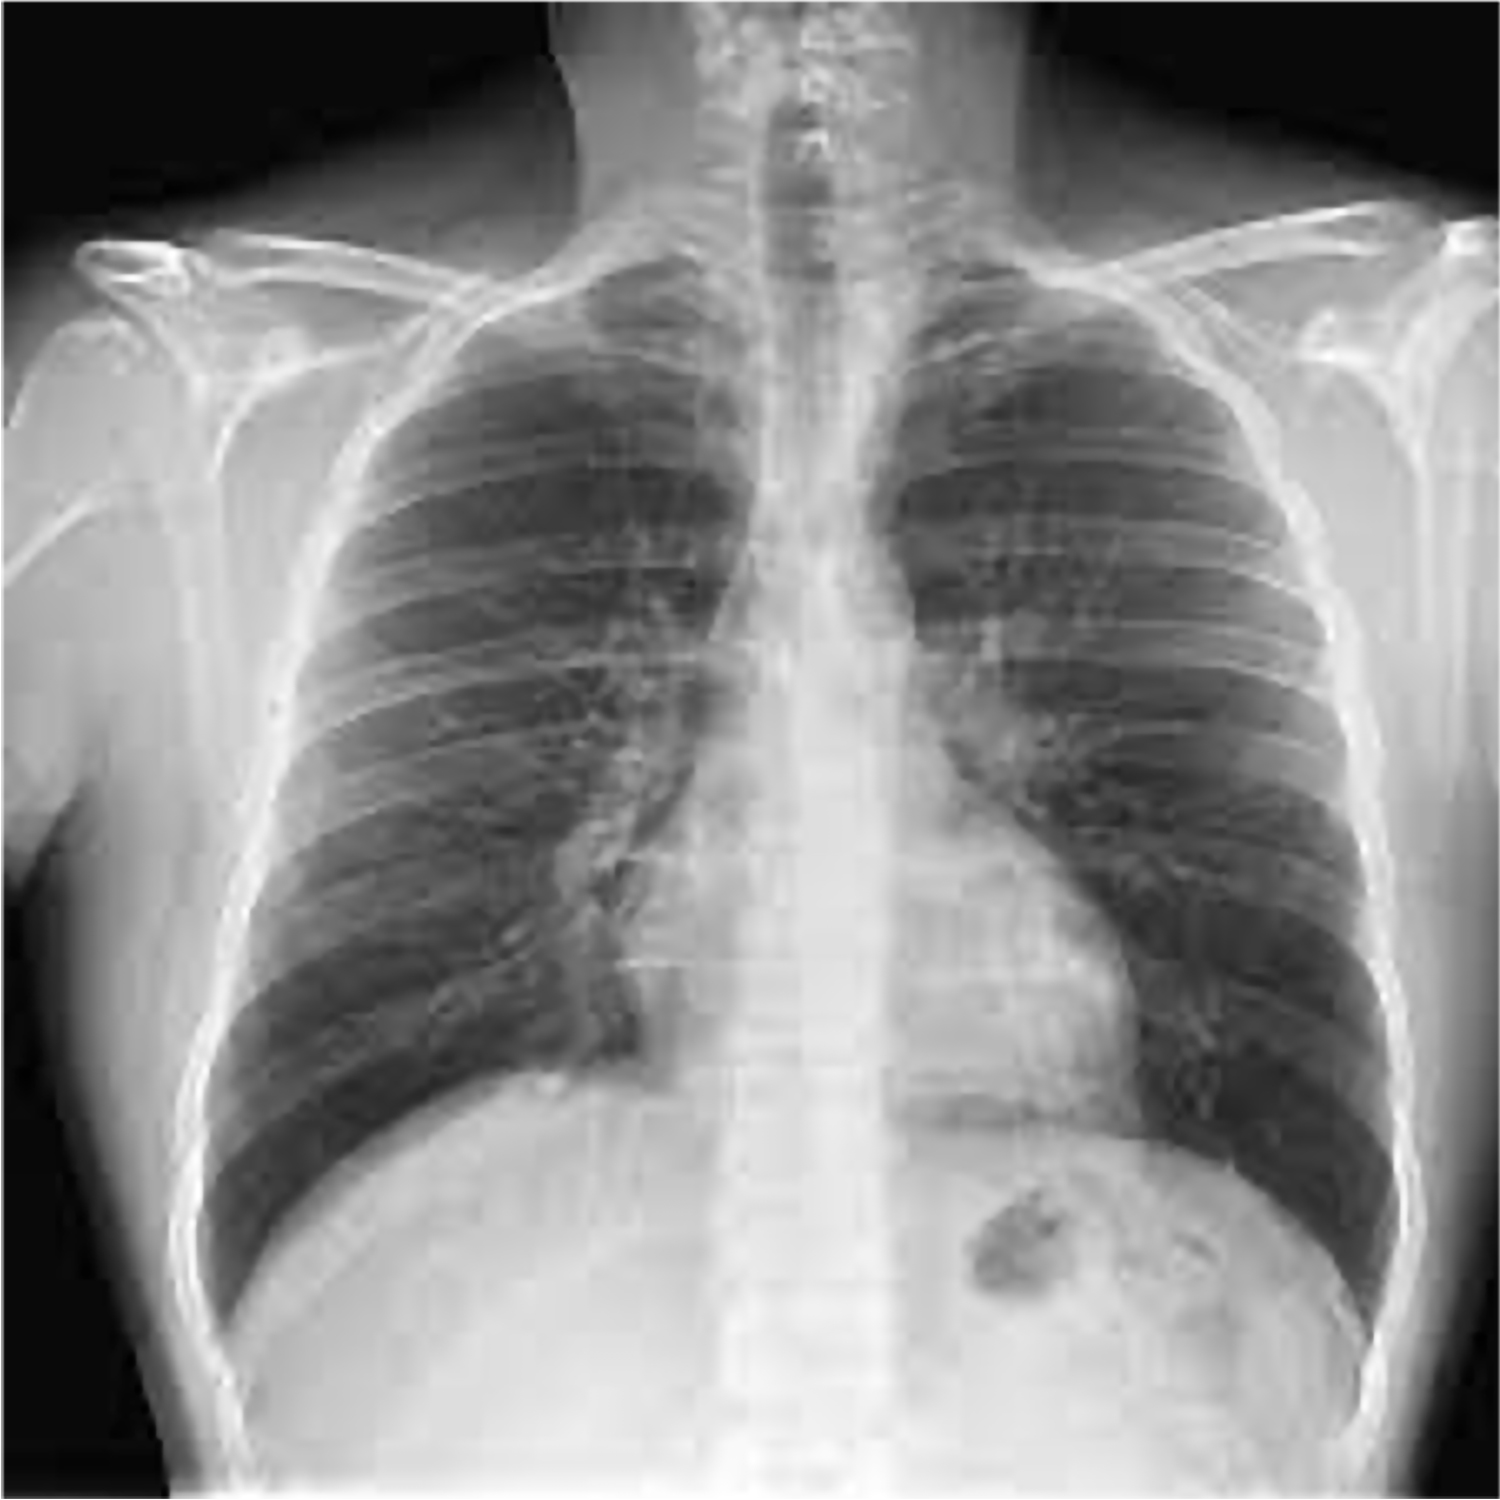

Pruebas previas

RX tórax: sin hallazgos relevantes